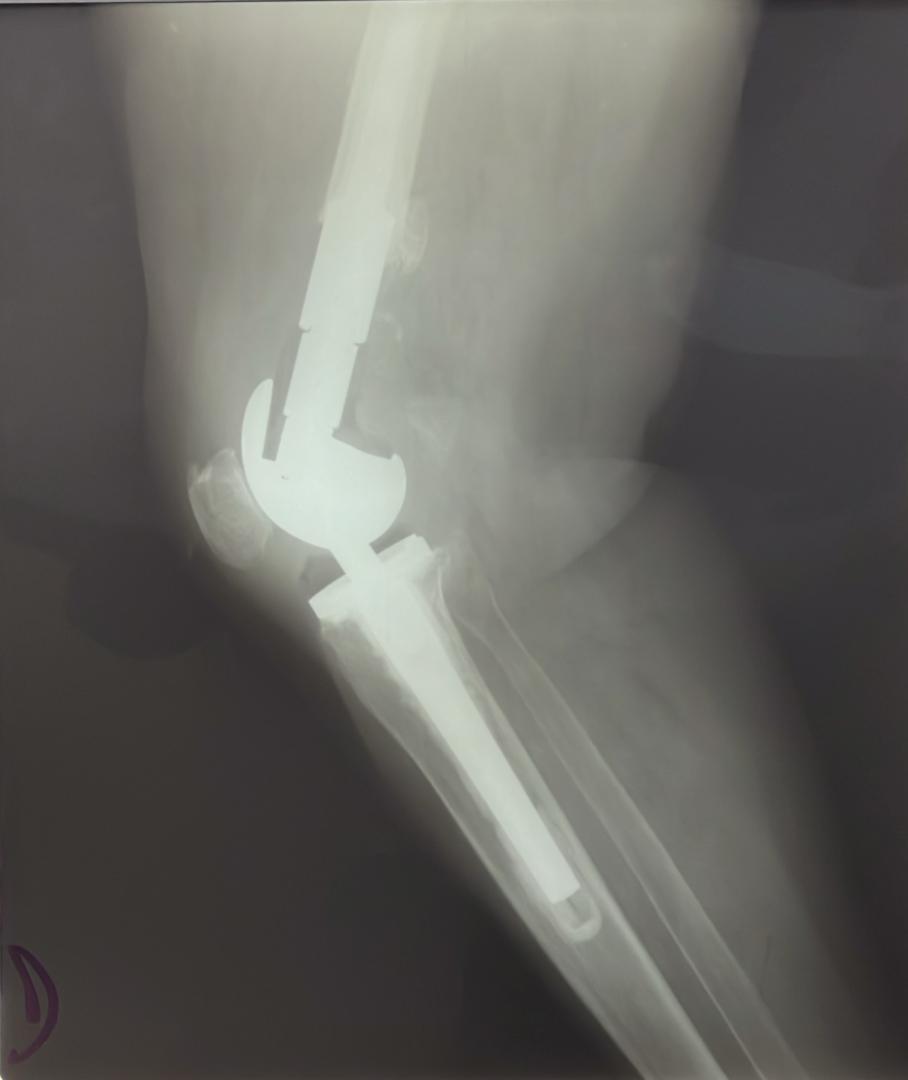

Galerie d’implants & imagerie

Exemples pédagogiques de prothèses et d’ostéosynthèses pratiquées à la CCL.

Genou — charnière (profil)